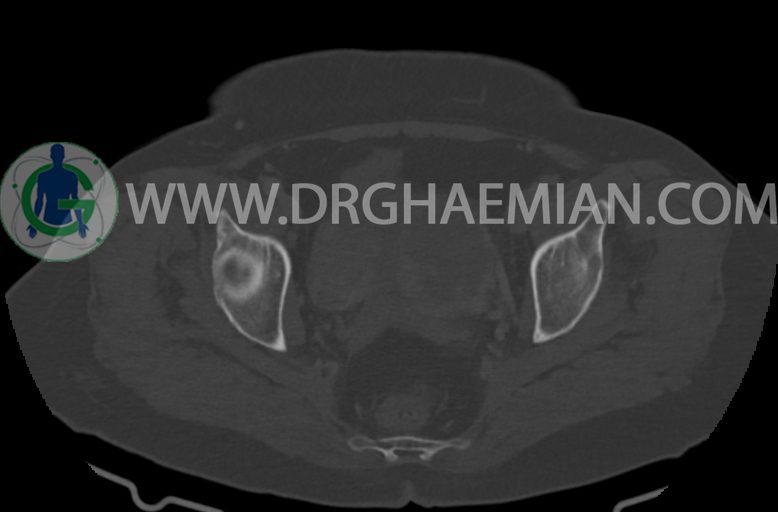

مایع آزاد در حفره شکم و لگن رویت نمی شود. ضایعه ای در مثانه مشهود نیست.

–ضایعه ی mass like هیپردنس- هتروژن به قطر 42mm در سمت راست لگن

–تغییرات DJD در L5/S1

مشهود است.